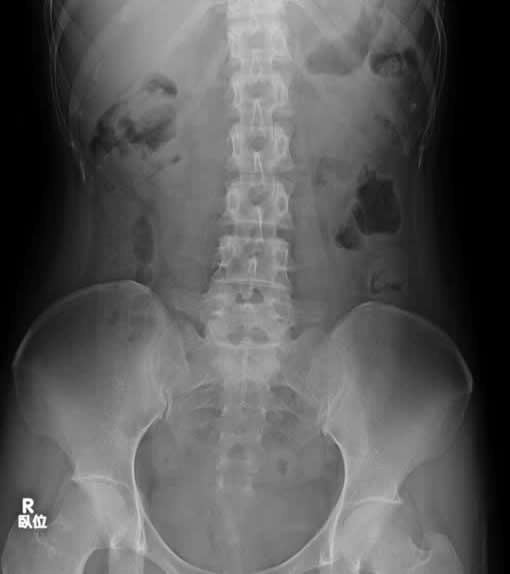

胸部、腹部、全身の骨・関節の撮影を行っています。当院では、FPD(フラットパネルディテクタ)システムにより、画像はデジタル化されており、被ばく低減や画質の安定性を実現しています。

腹部